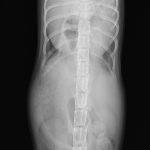

先天性心嚢横隔膜ヘルニア

若い猫が、普段はとても元気だけど、遊んだ後などに咳をする。呼吸が早くなる時がある。などの呼吸器症状で主治医を受診しました。エックス線検査の結果、心嚢横隔膜ヘルニアと診断されました。主治医より、外科的な対応のため紹介受診となりました。腹部正中切開の後、心嚢内に逸脱した、肝臓、胆嚢、小腸を腹腔内に戻し、横隔膜を再建しました。術後には、再拡張性肺水腫という病態が発生する可能性があるため、24時間体制で、患者さんを見守ります。幸い、肺水腫の傾向はみられず、5日目に無事に退院となりました。周術期には一時的に低酸素症に陥ったり、二酸化炭素濃度が上昇したりと、不安定な場面もありましたが、小さな体で本当によく頑張ってくれました。これで、普通の子猫としてどんどん大きく成長してくれると思います。本当によかった。